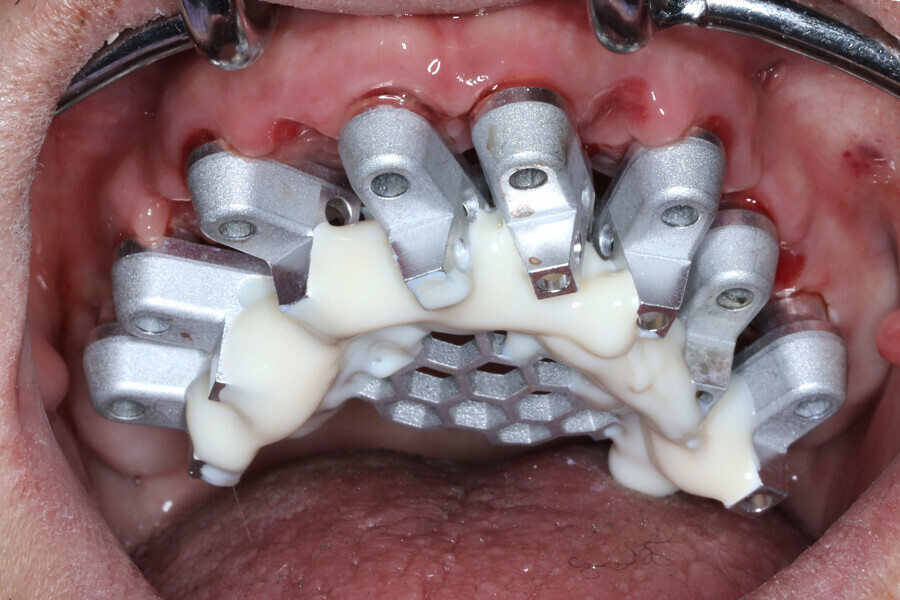

The analogue–digital process utilises MUA-compatible scan bodies (OptiSplint) designed to incorporate an aluminium mesh frame (Fig. 3a) that can be customised chairside (with the snipping tool included) as required by the intra-oral location of the implants. This mesh frame comes in small and large sizes to accommodate various mouth sizes and MUA–implant positions. The workflow involves inserting the scan bodies on to the MUAs intra-orally (Fig. 3b). The proprietary scan bodies have extensions (Fig. 4) to allow the mesh to seat and rotate in close proximity to the extensions, which facilitate luting using a resin base material (STELLAR DC Acrylic, Taub Products). The structure can then be digitised by scanning intra-orally with an intra-oral scanner and extra-orally with an intra-oral scanner or desktop scanner. The bonded splinting of the scan bodies to the mesh frame allows for a simple uninterrupted scan path.

Fig. 3b: Completed Grammetry intra-oral structure secured to MUAs with conventional screws.